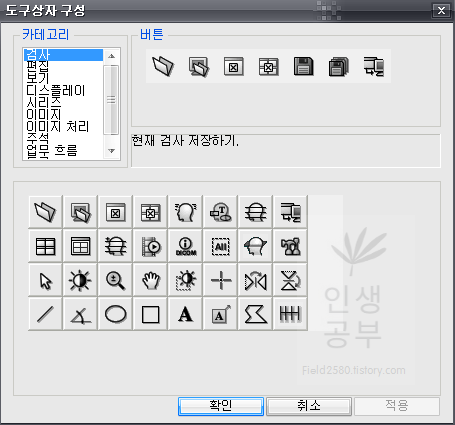

2. Display Workstation 도구상자 메뉴 설정방법

최상단에 있는 메뉴 중 도구를 눌러줍니다.

도구상자 구성을 눌러줍니다.

위와 같은 도구상자 구성 화면이 뜨게 됩니다. 아래에는 현재 사용중인 도구상자들이고 왼쪽 상단에는 도구상자에 넣을 수 있는 카테고리들이 있습니다. 카테고리칸 옆에는 버튼칸이 있고 아래 도구상자칸에 없는 메뉴들도 많이 있습니다. 아이콘에 마우스를 가져다 대면 간단한 설명이 나오니 필요하신 분들은 한번씩 다 확인해보시는 걸 추천해드립니다.

저 같은 경우는 Cobb 각도를 많이 사용하기 때문에 우선 Cobb각도 설정하는 방법에 대해서 알려드리겠습니다. 카테고리칸에 주석을 눌러주면 다양한 각도나 선, 모양을 그릴 수 있는 버튼이 나옵니다. 그중 상단 3번째 있는 버튼이 Cobb각도 그리기 입니다.